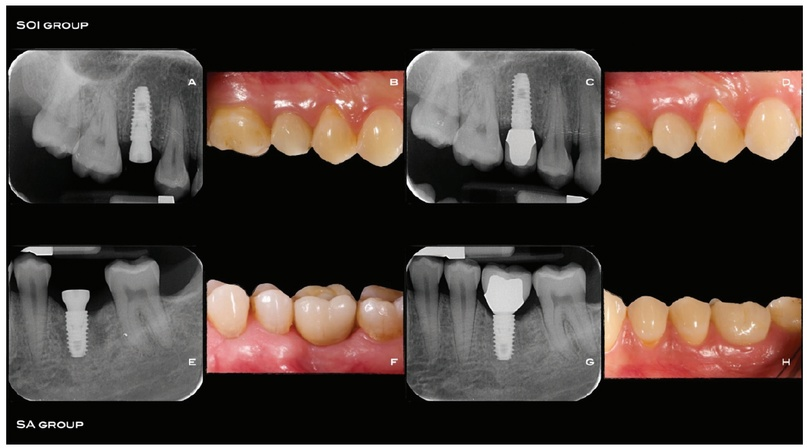

Последовательность этапов лечения приводится на рис. 2a-2h. Коэффициент стабильности имплантатов (ISQ) измеряли с помощью частотно-резонансного анализа, используя штифт multipeg (Hiossen; Энглвуд Клиффс, США) и аппарат IS3 Monitor (Hiossen). Формирователи десны на имплантатах фиксировали ручной отверткой. Края раны ушивали швами. В послеоперационном периоде пациентам назначали антибиотики (1 г амоксициллина или 600 мг клиндамицина в случае аллергии на пенициллин) дважды в день в течение 5 дней и 600 мг ибупрофена при необходимости. Повторные измерения ISQ выполняли каждую неделю в течение 8 недель после имплантации, а затем - через 12 недель, как и в ранее опубликованном исследовании. Для оценки ISQ удаляли формирователи десны и поочередно фиксировали штифты multipeg в каждом имплантате. ISQ измеряли дважды: вестибулярно-орально и мезиально-дистально. После чистки и дезинфекции в 0,2% растворе хлоргексидина и ультразвуковой ванночке формирователи десны повторно фиксировали на имплантатах с помощью ручной отвертки. Оттиски для изготовления окончательных реставраций получали через 8 недель после имплантации.

Рис. 2a-2h. a-d: последовательность этапов лечения в группе S01: установка имплантата (а), фиксация протеза через12 недель после имплантации (Ь), прицельная рентгенограмма после фиксации протеза (с), клинический снимок через 4 месяца (d). E-h: последовательность этапов лечения в группе SA: установка имплантата (е), фиксация протеза через 12 недель после имплантации (f), прицельная рентгенограмма после фиксации протеза (g), клинический снимок через4 месяца (h)